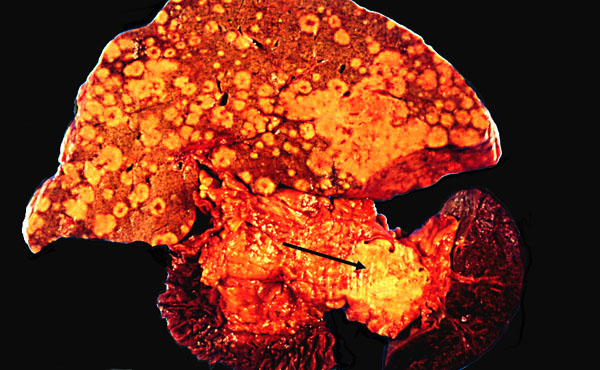

Carcinoma of the tail of the pancreas with numerous liver metastases, gross